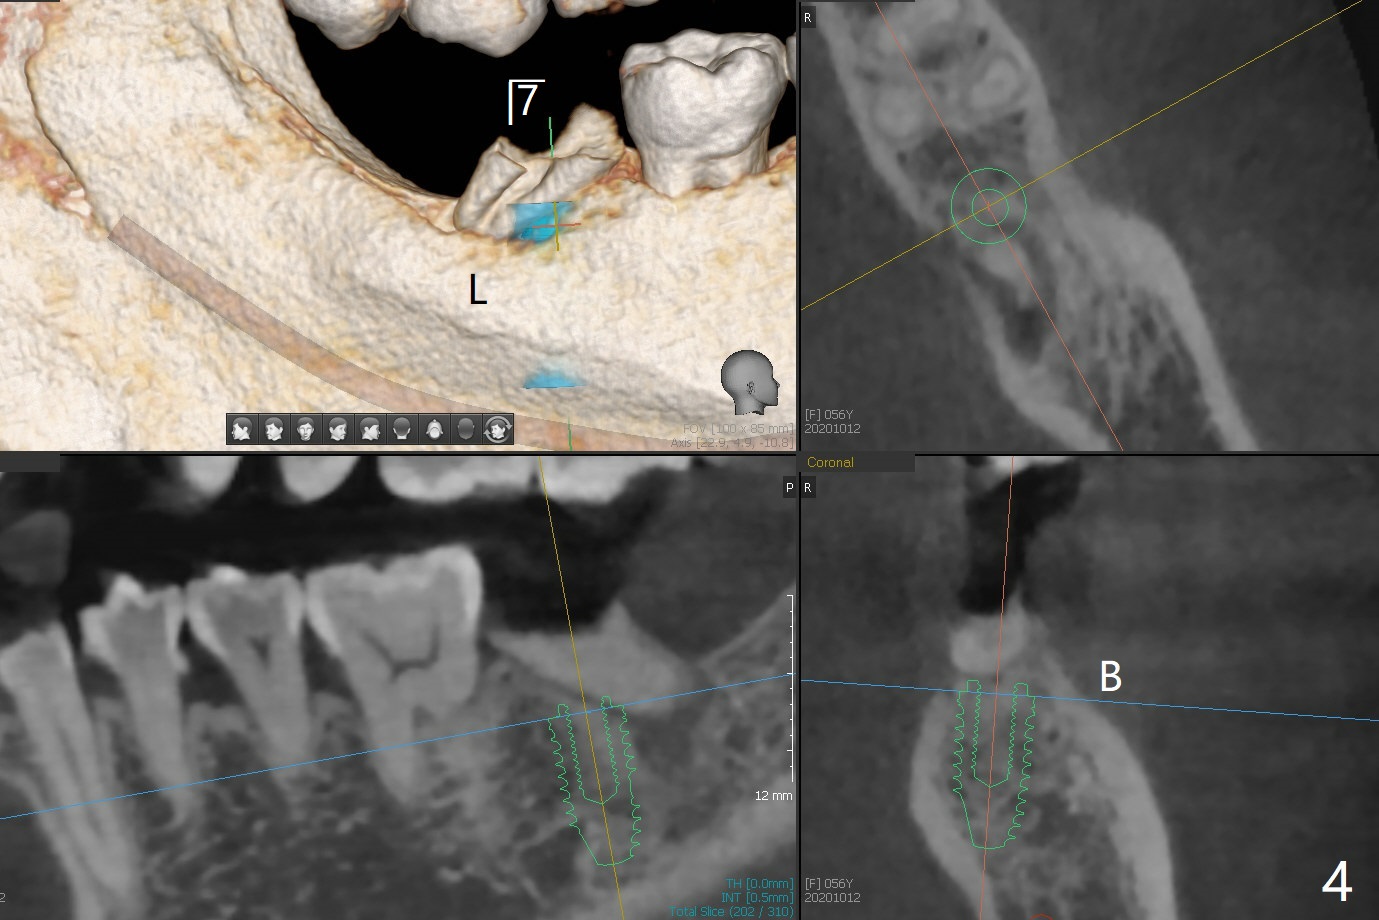

56岁女右侧不好咀嚼,右下7远中龈下龋齿(图一,二),能保留吗?Implant or rct plus crown lengthening, either way is fine, but implant may be more straightforward (Robert). Hi, Jennifer: I love the way you design implant in the mesial slope of the lower 2nd molar (Fig.1,4). When I place an implant free hand, I make sure that the long axis of the implant is 5 mm from the distal surface of the 1st molar (half of the mesiodistal width of the 2nd molar, Fig.5) as long as the implant is not too close to the neighboring root (black dashed line of Fig.5). PAs are taken several times intraoperatively to monitor the distal drifting (Fig.6 open arrow) of the osteotomy (red line). In my opinion, the drifting exists with guided surgery, especially the change of angulation. Can you intentionally move the implant mesially (Fig.7 open arrow) by 0.5-1 mm depending upon bone density or tilt the implant mesial coronally? Thanks for your consideration.